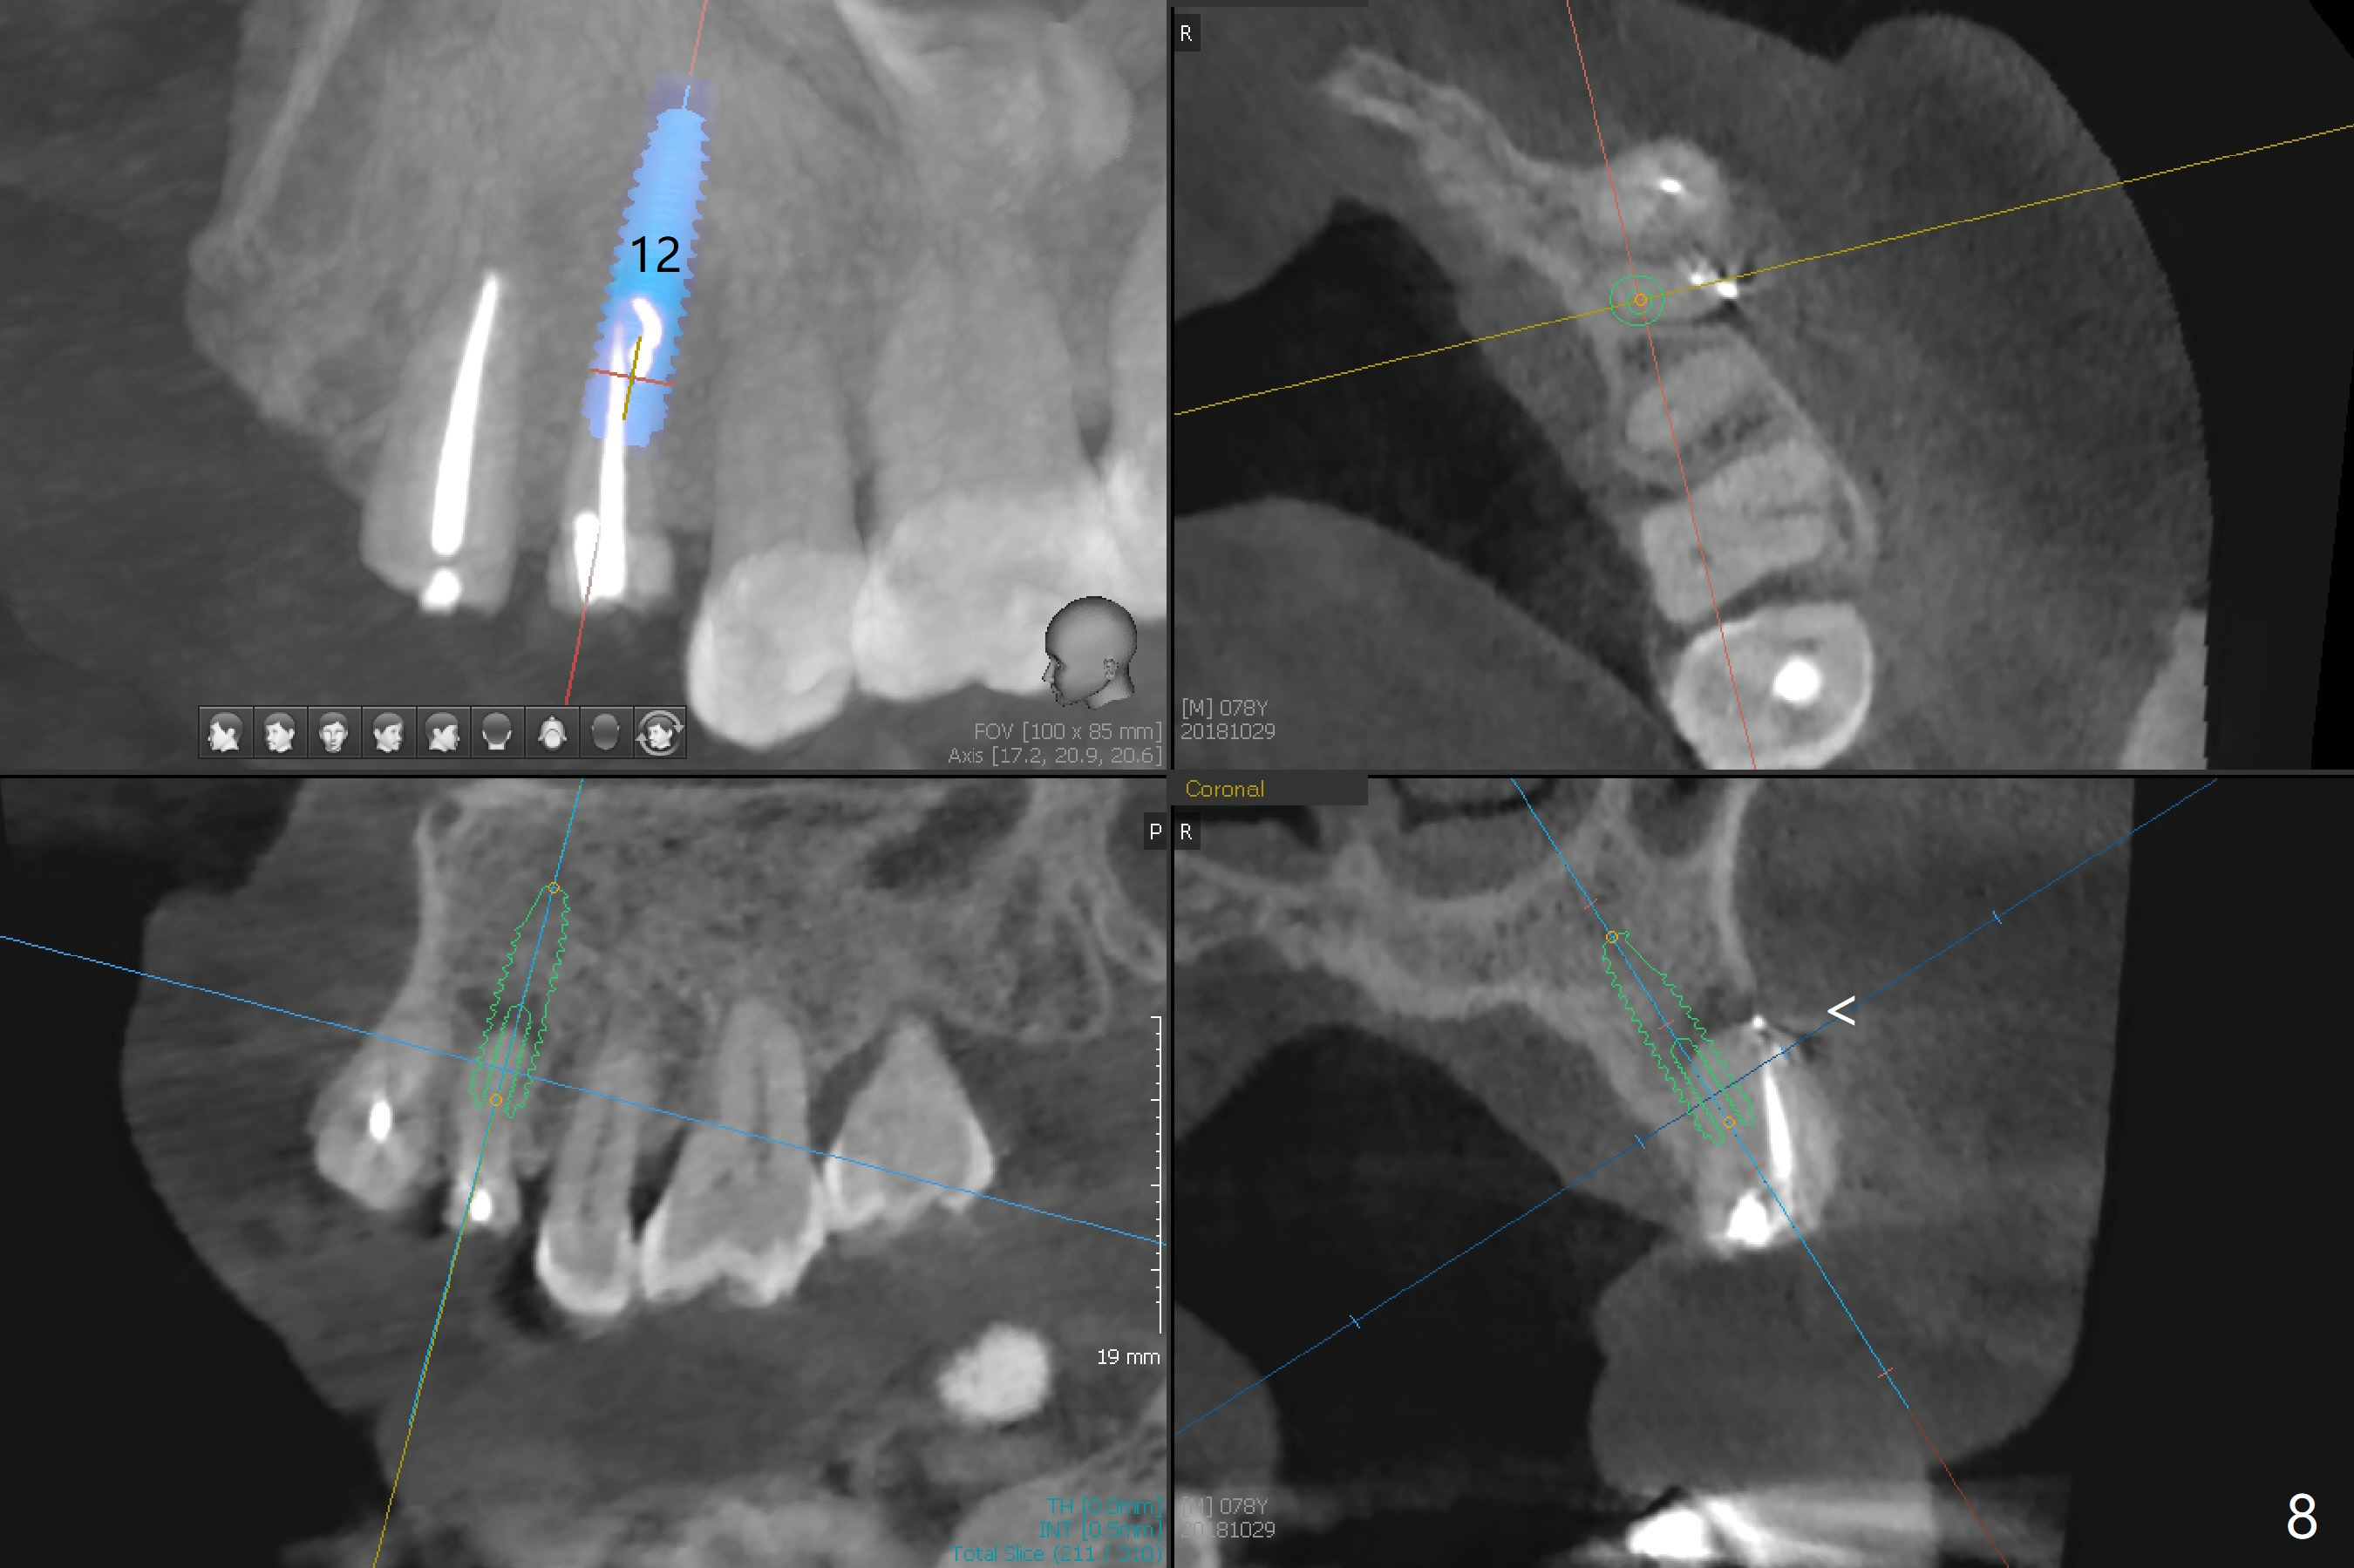

A 78-year-old man's 8 unit FPD dislodges (#5-12, Fig.1). Three of 4 abutments seem to be non-salvageable (#6,11,12 fractured equigingival, extraction, immediate implants). For restoration, implant will be placed at #8 and 9 as well. Implant FPDs will be fabricated at #6-8 and 9-11 (Fig.2) with #5 (with build up or prefabricated post) and 12 single unit crowns to better withstand deep overbite and overjet. After discussion with lab, a major change will be implants to be placed at #7 and 10 instead of #8 and 9 (narrow ridge). The implant at #7 will be a 1-piece (3 mm in diameter), whereas the rest 2-piece (3.5 mm). The abutment of IS 1-piece implant is 10 mm in length, while that of DIO's 5 mm. The former will be used if the vertical space is sufficient.